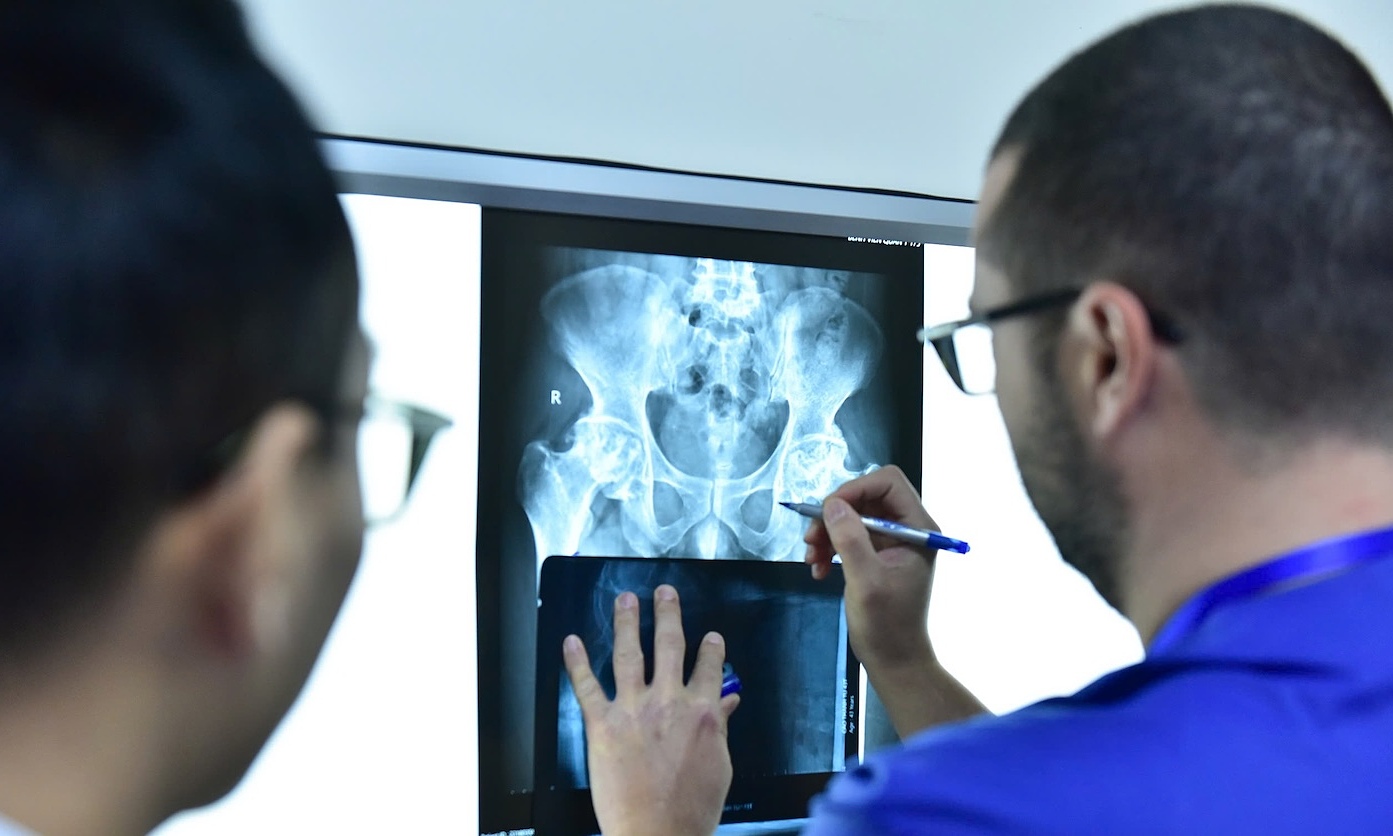

A trend of younger patients undergoing initial hip surgeries, combined with rising average life expectancy, is projected to significantly increase the demand for hip revision surgeries in Vietnam over the next decade.